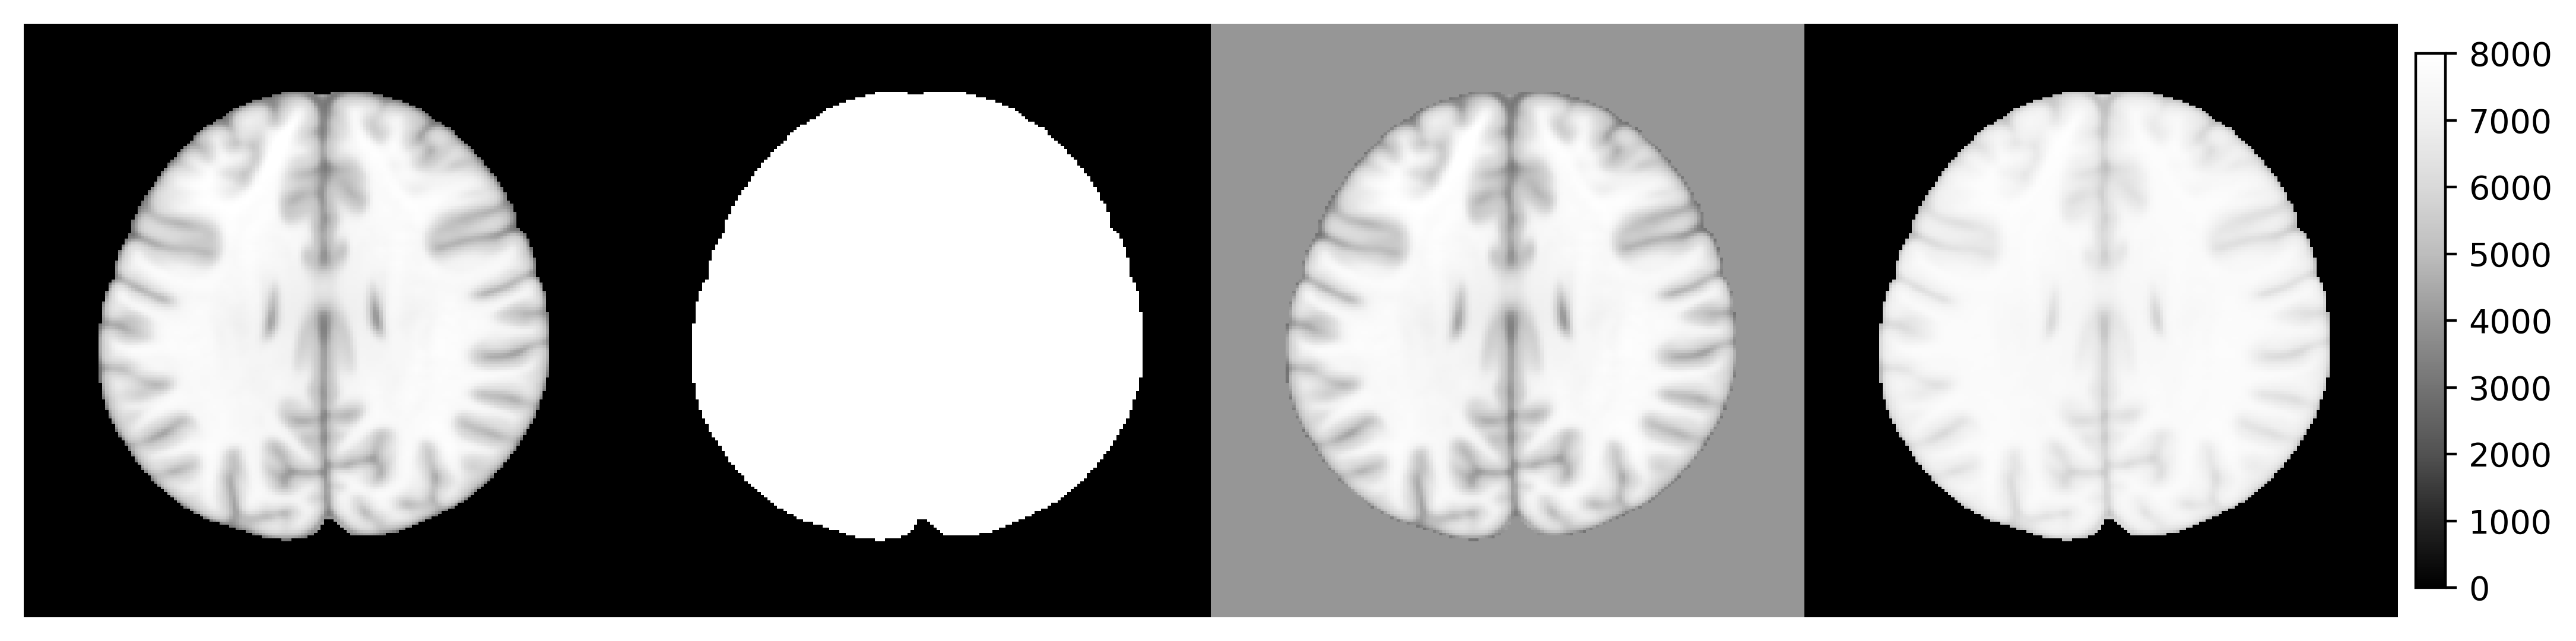

what is S3 generic, see the following examples:

library(rpyANTs)

image <- ants$image_read(ants$get_ants_data('mni'))

print(image)

dim(image)

range(image)

y1 <- (image > 10) * 8000

y2 <- image

y2[y2 < 10] <- 4000

y3 <- log(image + 1000)

y3 <- (y3 - min(y3)) / (max(y3) - min(y3)) * 8000

ants_plot_grid(

list(image, y1, y2, y3),

slices = 100, shape = c(1, 4),

vmin = 0, vmax = 8000

)